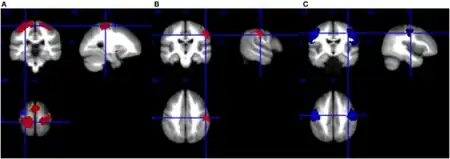

a)MND had significant hyperactivity in the left postcentral gyrus and right precentral gyrus b) hyperactivity in right postcentral gyrus during right-hand movement c)hypoactivity in bilateral precentral gyrus at rest